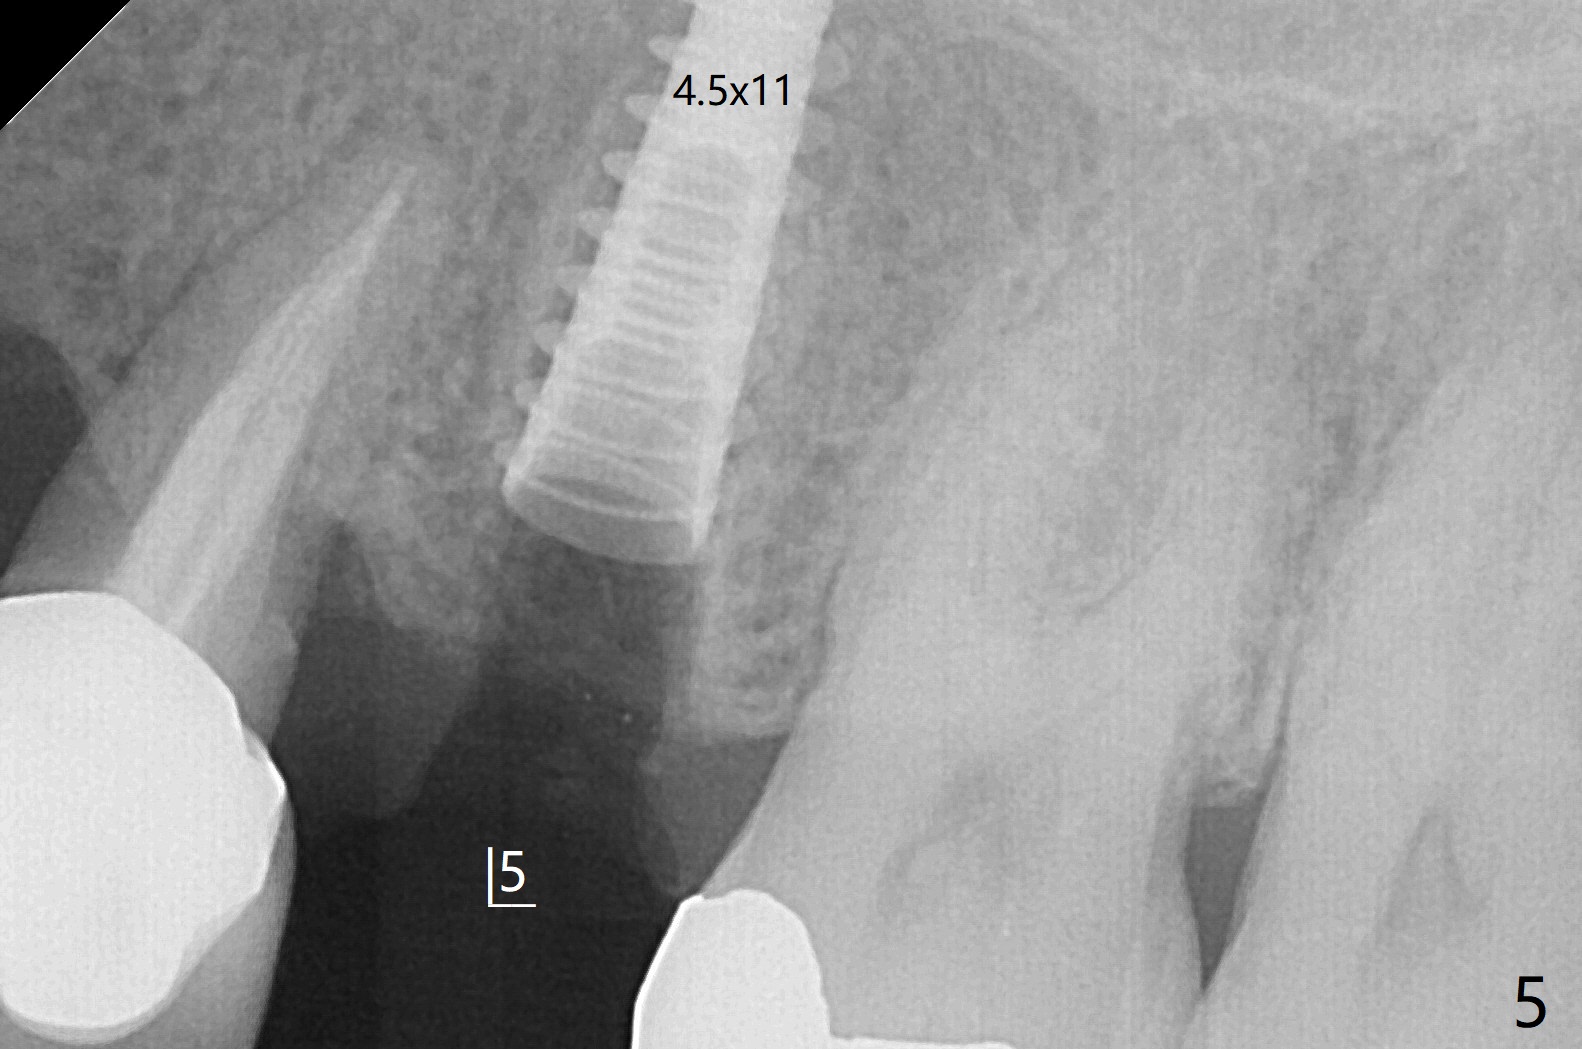

害怕病人局麻药很慢起效,术中身体会动,术中决定减小右下6,7植体直径0.5毫米(与导板设计相比),一旦植体越过牙槽嵴顶骨皮质,稳定性突然减低(图一)。尽管扭力10-15Ncm,为了避免二期手术,放置愈合基台(图二),6基台没有就位(箭头),因为植体种太深了,牙槽骨阻挡(*)基台就位。当取出6基台时,植体一起旋出,重新植入时,就没有种那么深(图三:箭头,与图一,二对比)。由于扭力低,只好放置愈合帽,骨粉(*),GEM Cap(6-9月胶原膜)和牙周胶水。由于导板设计缘故,左上5拔除,种植后,才开始左上3一段式植体植入(图四),5也植入太深(图五),必须放置最小直径最长袖(cuff)的基台(图六),今后导板即刻植牙先不要到达设计深度。术后一周CT显示尖牙植体位于牙槽骨内(图七 (>:腭侧牙槽嵴))。Bone graft fills in the buccal apical defect at #13 one week postop (Fig.8 <). 术后两个月左上3临时牙冠折裂,5松动(图九,十),后者取出衬里,软组织愈合。术后8个月左上3,5取模,右下6 uncover,愈合帽表面覆盖骨质,把7号牙愈合基台放到6号牙上,而7号牙放置4.5x4(4)毫米修复基台,固定牙周敷料,这样6号牙伤口不必缝合。术后8.5个月右下6放置4.5x7.5(4)毫米基台,发现7基台没有就位(图十一:箭头),通过旋转7 基台,终于就位(图十二),螺丝往下移位(与图十一:横线对比),但是基台边缘太低,不利于取模。改用5.5x4(5)毫米UF基台,临床上不能就位,局麻使用5.5毫米Profile Drill后,才能就位(图十三),螺丝下端超越最低螺沟(横线)。